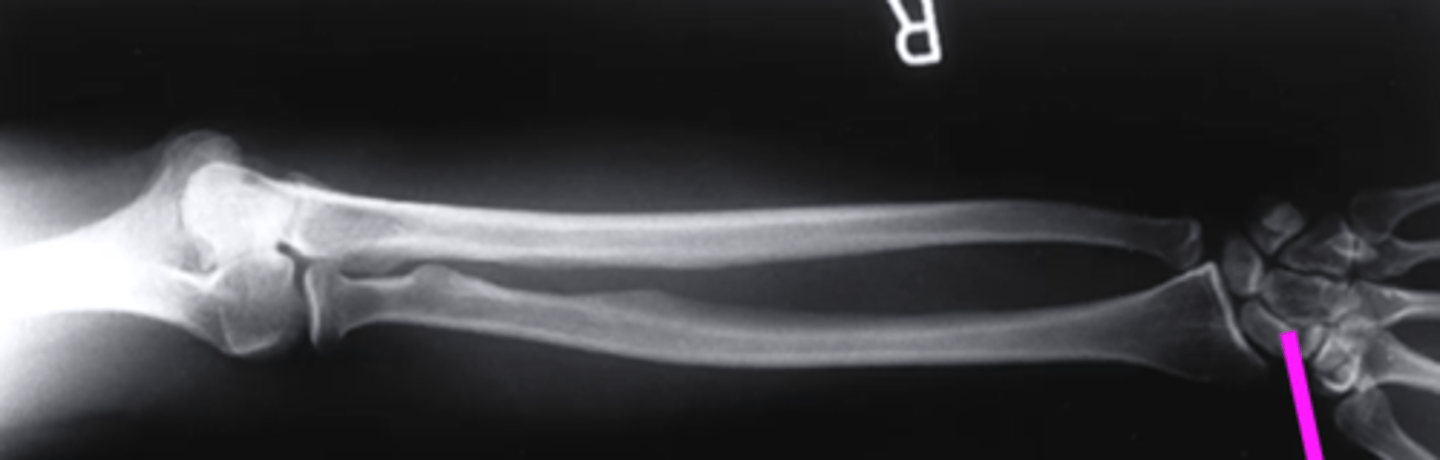

lateral forearm

what view is this

olecranon process

what does this pink line point to?

ulna

radius

radiocarpal joint